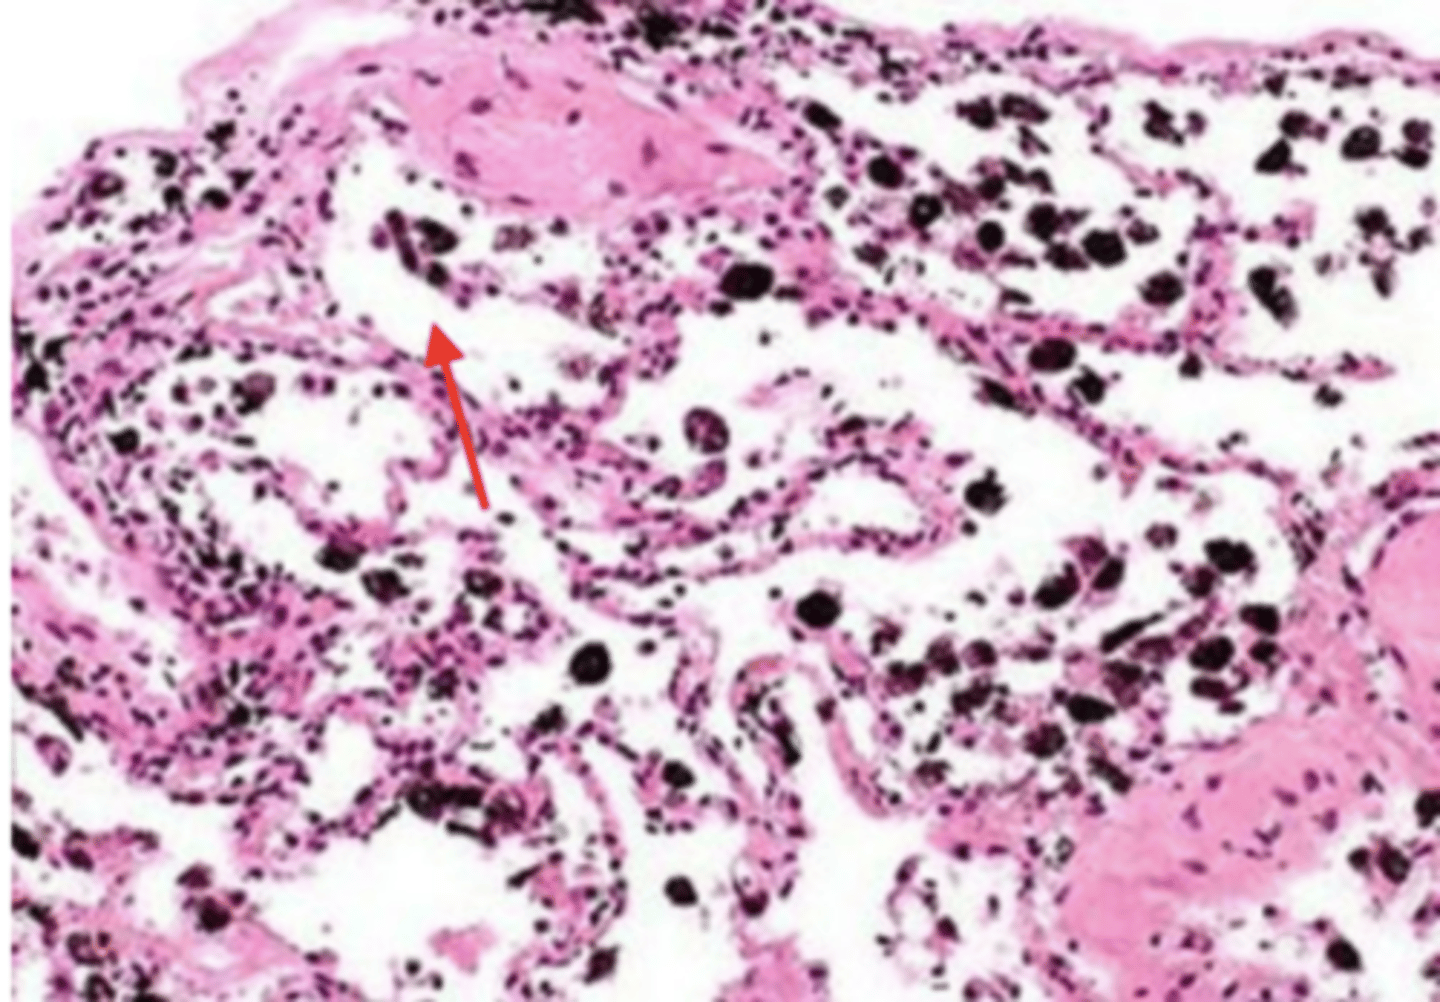

smoker's lung

alveolus (of smoker's lung)

carbon deposits (tar)